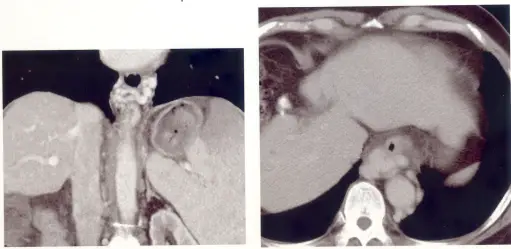

62歲的楊先生,罹患 B 型肝炎已十多年,每年到醫院追蹤檢查。這次醫師為他開立電腦斷層掃描,發現有異常如圖示。則楊先生最有可能罹患:

本題核心在於運用腹部電腦斷層(CT)影像判讀慢性肝臟病變的形態學改變,特別是肝硬化(liver cirrhosis)常見的「萎縮-肥大複合體」(atrophy–hypertrophy complex)及肝表面結節化(surface nodularity)。

從左側冠狀面CT影像可觀察到:

- 肝臟表面呈現不規則結節狀輪廓,肝邊緣不平滑,伴有多處凹陷(regenerative nodules造成的表面凹凸)

- 相對於右側肝葉明顯縮小,尾狀葉(caudate lobe)明顯增大

- 腹主靜脈附近脂肪間隙增寬(porta hepatis fat widening)

右側橫切面CT影像則顯示:

- 肝表面多處凹凸不平且可見小結節影(regenerative nodules),肝臟質地不均

- 尾狀葉位於脊柱前方的部分比左右肝葉更為突出

- 左右肝葉相對大小不對稱:右葉縮小、左側外側葉有增生趨勢

這些特徵符合慢性肝臟纖維化造成的肝臟形態改變。

- 選項A 肝硬化(liver cirrhosis)

CT典型表現包括肝表面結節化、不規則輪廓、右葉或中段萎縮、尾狀葉及左葉外側段肥大,門靜脈高壓表現(脾腫大、腹水、側支迴流)亦常合併出現。本題影像正符合上述形態學改變,故為正確答案 ([ctisus.com]